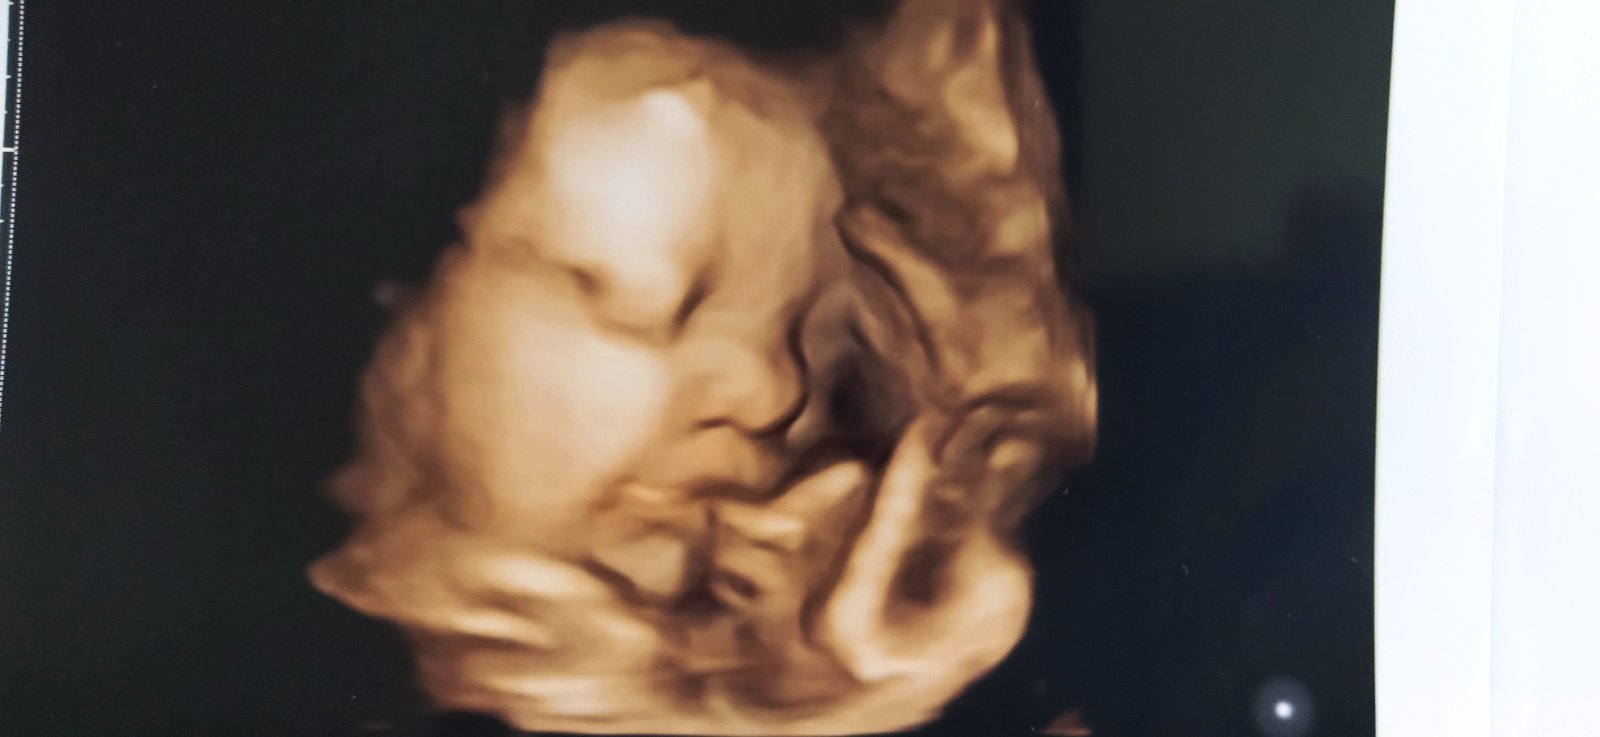

My tahame uz 28tt, brusko rastie jedna radost, mala kope ostosest tak som uz taka kludnejsia ked ju citim ako si tam tancuje☺️ fotku mam poslednu z 20tt aj to len taku nijaku, na 3D som nebola a o tyzden idem na dalsie sono tak snad uz bude aj fotka pekna☺️ tak aspon brusko pridam😃fotene pred dvomi dnami, uz mi je vsetko male a ja co som neznasala saty tak teraz len v satach chodim, vsetko ostatne ma tlaci a vadi mi na brusku🥴